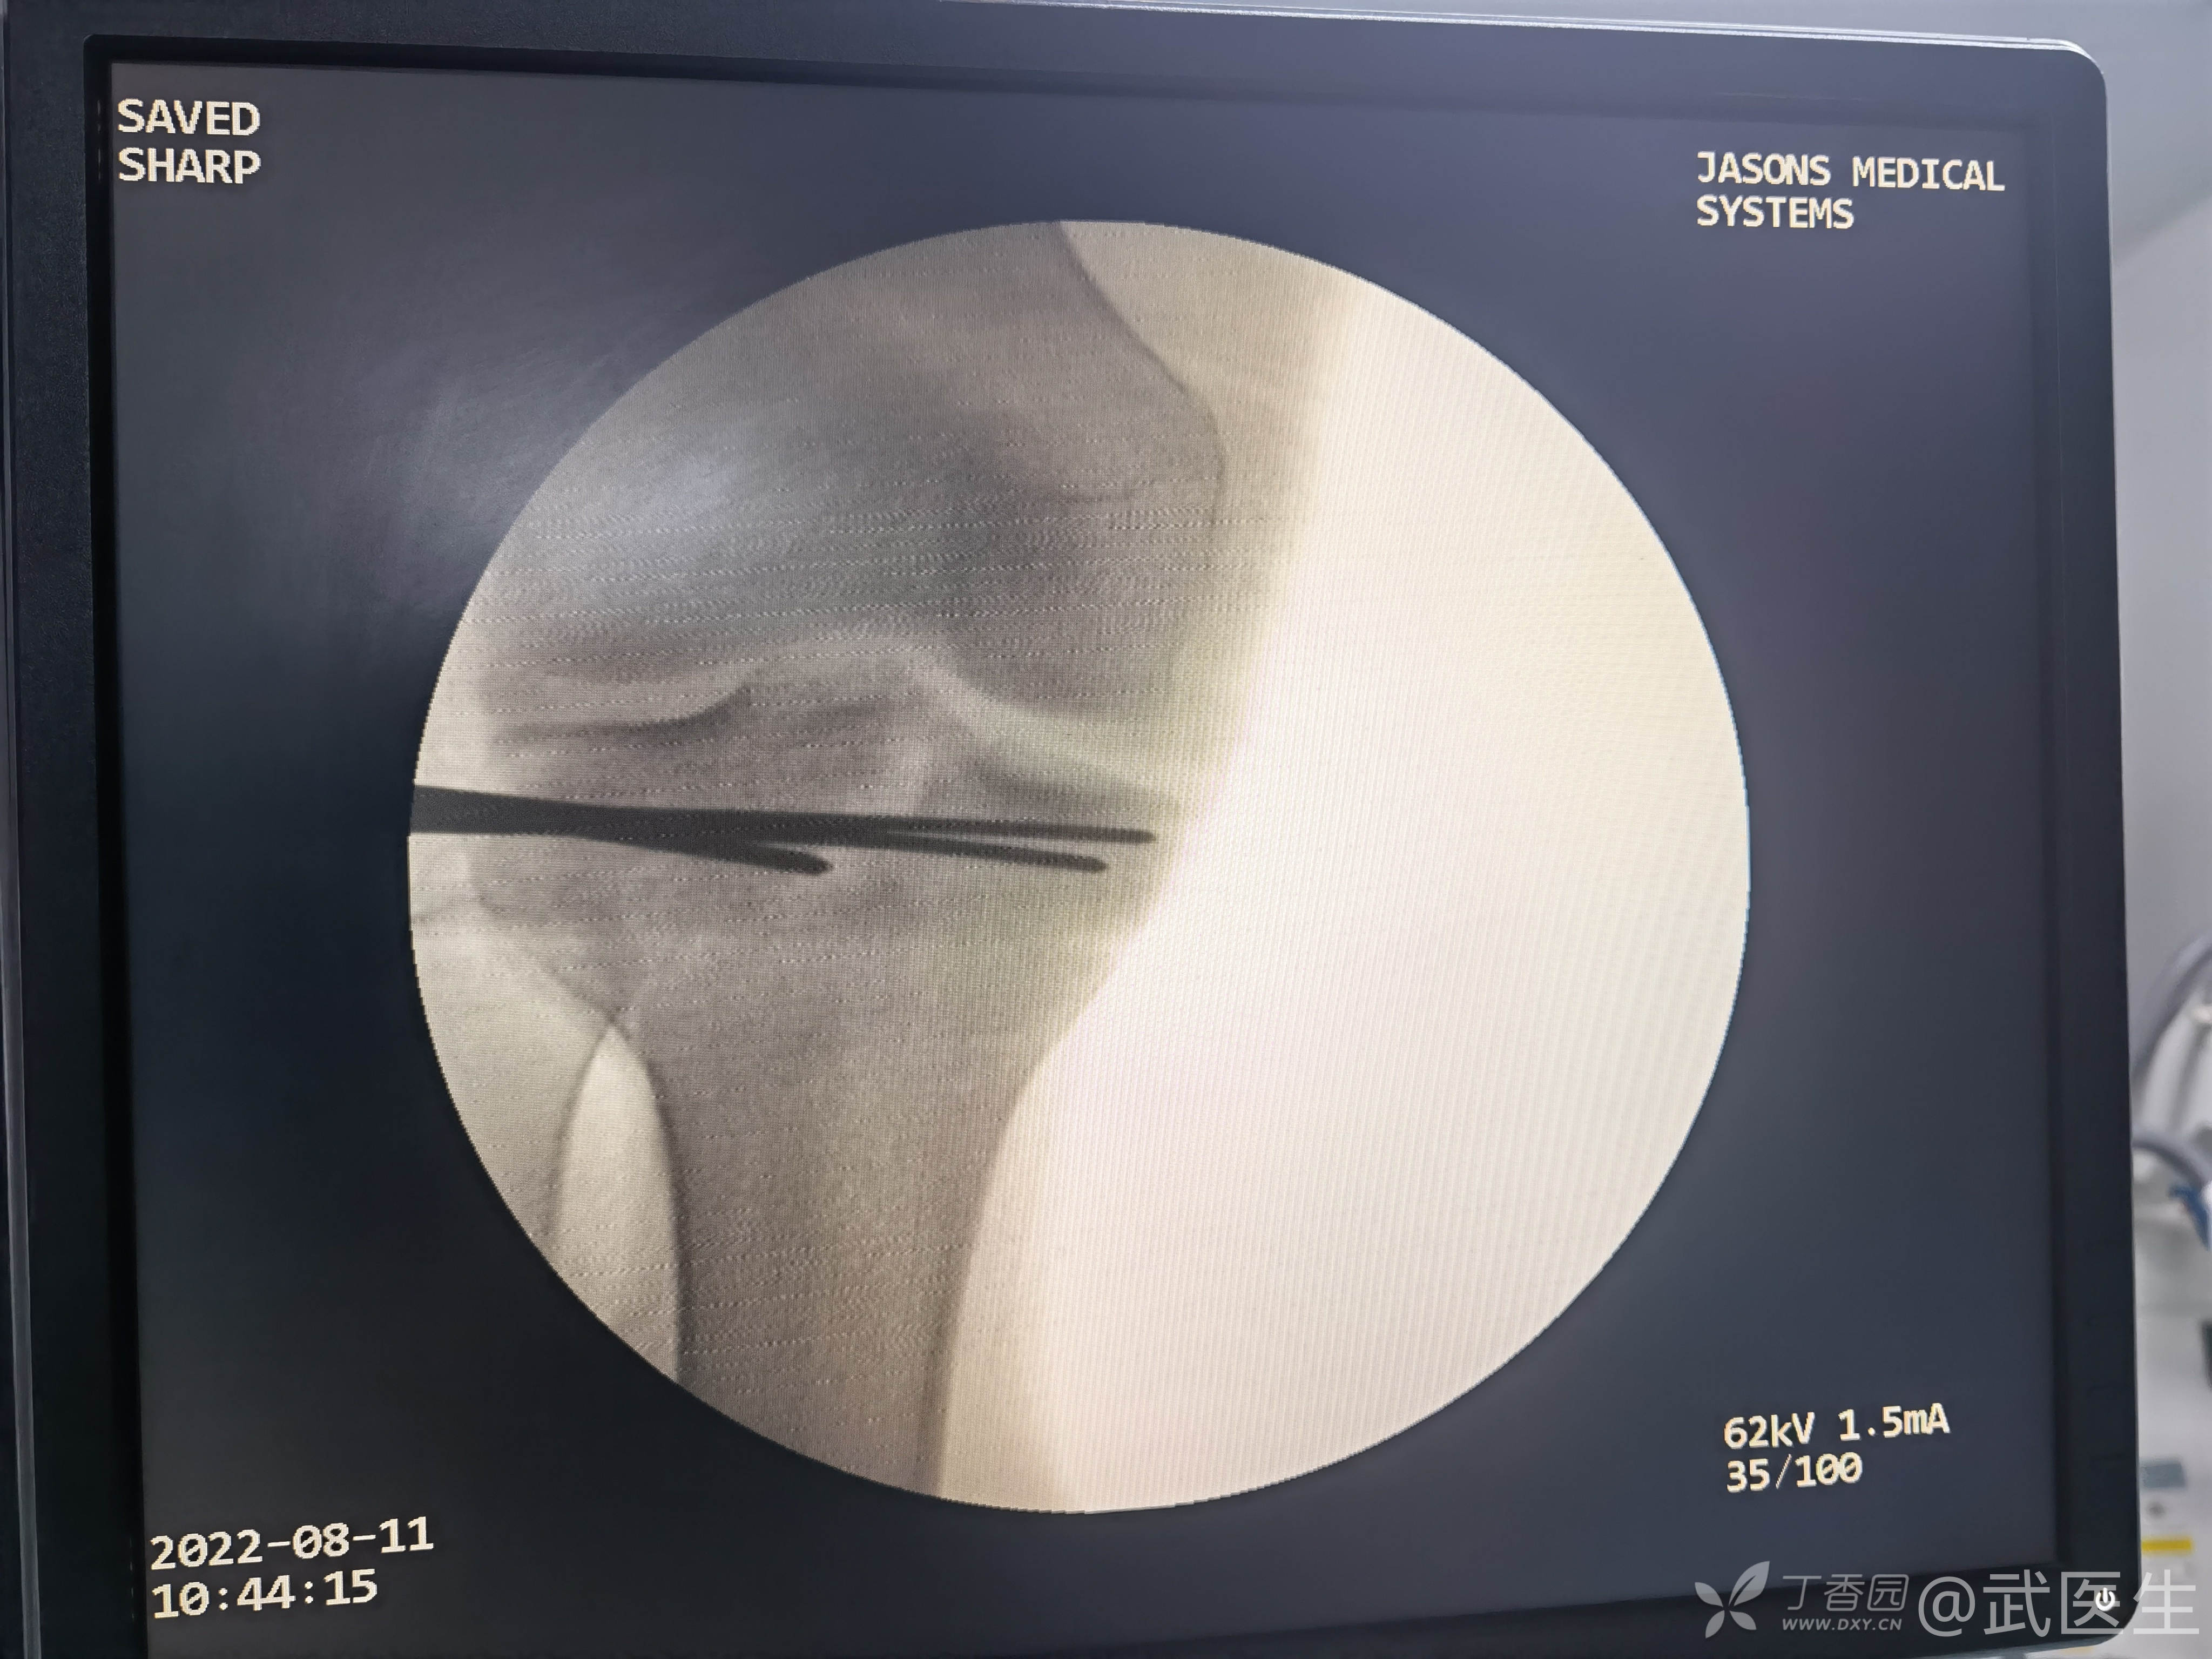

出现了题目中的一句话“但求義當先”,清理异物后创面VSD覆盖,择期骨折内固定

15岁,骨骺存在,关节加压固定,外侧板支撑